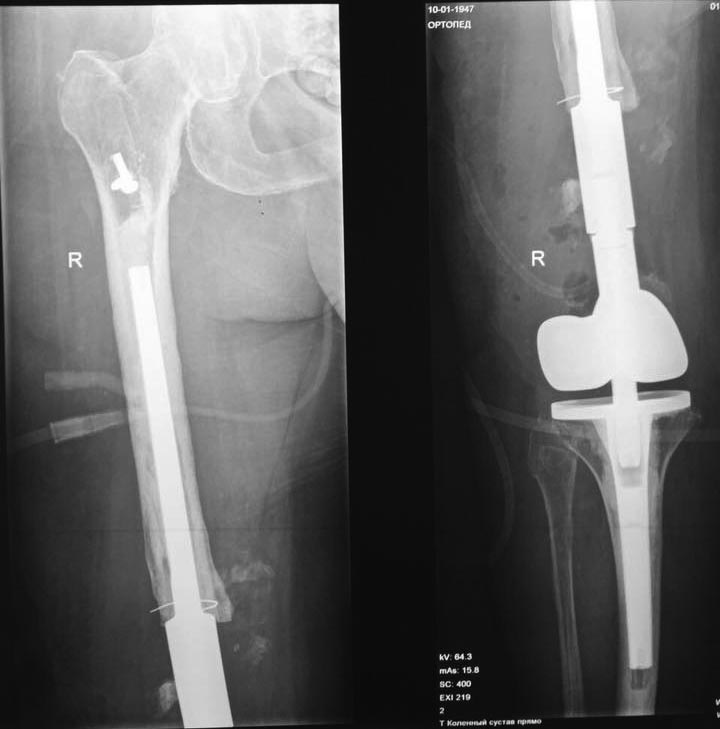

[Ortho] Несращение бедра

Закончили полемику, пациентка активизирована